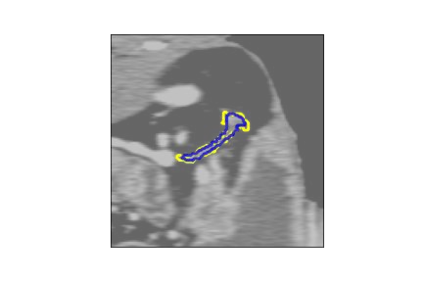

The human annotations are imperfect, especially when produced by junior practitioners. Multi-expert consensus is usually regarded as golden standard, while this annotation protocol is too expensive to implement in many real-world projects. In this study, we propose a method to refine human annotation, named Neural Annotation Refinement (NeAR). It is based on a learnable implicit function, which decodes a latent vector into represented shape. By integrating the appearance as an input of implicit functions, the appearance-aware NeAR fixes the annotation artefacts. Our method is demonstrated on the application of adrenal gland analysis. We first show that the NeAR can repair distorted golden standards on a public adrenal gland segmentation dataset. Besides, we develop a new Adrenal gLand ANalysis (ALAN) dataset with the proposed NeAR, where each case consists of a 3D shape of adrenal gland and its diagnosis label (normal vs. abnormal) assigned by experts. We show that models trained on the shapes repaired by the NeAR can diagnose adrenal glands better than the original ones. The ALAN dataset will be open-source, with 1,594 shapes for adrenal gland diagnosis, which serves as a new benchmark for medical shape analysis. Code and dataset are available at https://github.com/M3DV/NeAR.